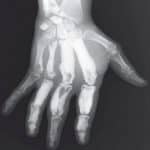

Bệnh nến xương còn gọi là bệnh Leri là một loạn sản xơ xương hiếm gặp. Tỷ lệ mắc bệnh là 0,9/1 triệu dân. Hiện nay vẫn chưa xác định được nguyên nhân gây ra bệnh này. Theo y văn, ca bệnh được ghi nhận đầu tiên cách đây gần 100 năm. Đây không phải là bệnh ác tính. Vì thế, phương pháp điều trị được chọn lựa chính là phẫu thuật khi bệnh tiến triển…